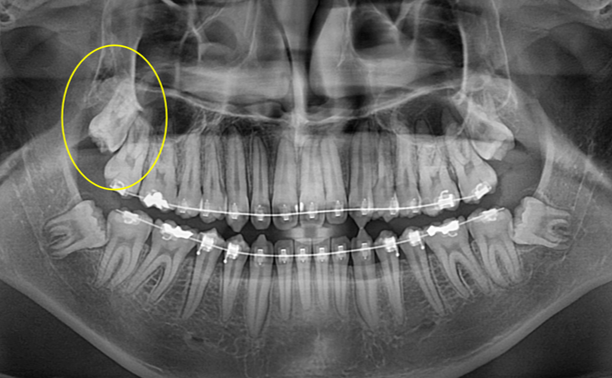

상악 깊이 매복된 사랑니 발치

Before

위쪽 깊숙히 매복된 사랑니는 때로 발치하기가 까다로울 때가 있습니다.

뿌리가 벌어진 채로 4개나 있는 어려운 치아였지만

다행히 큰 문제 없이 잘 발치되었습니다.